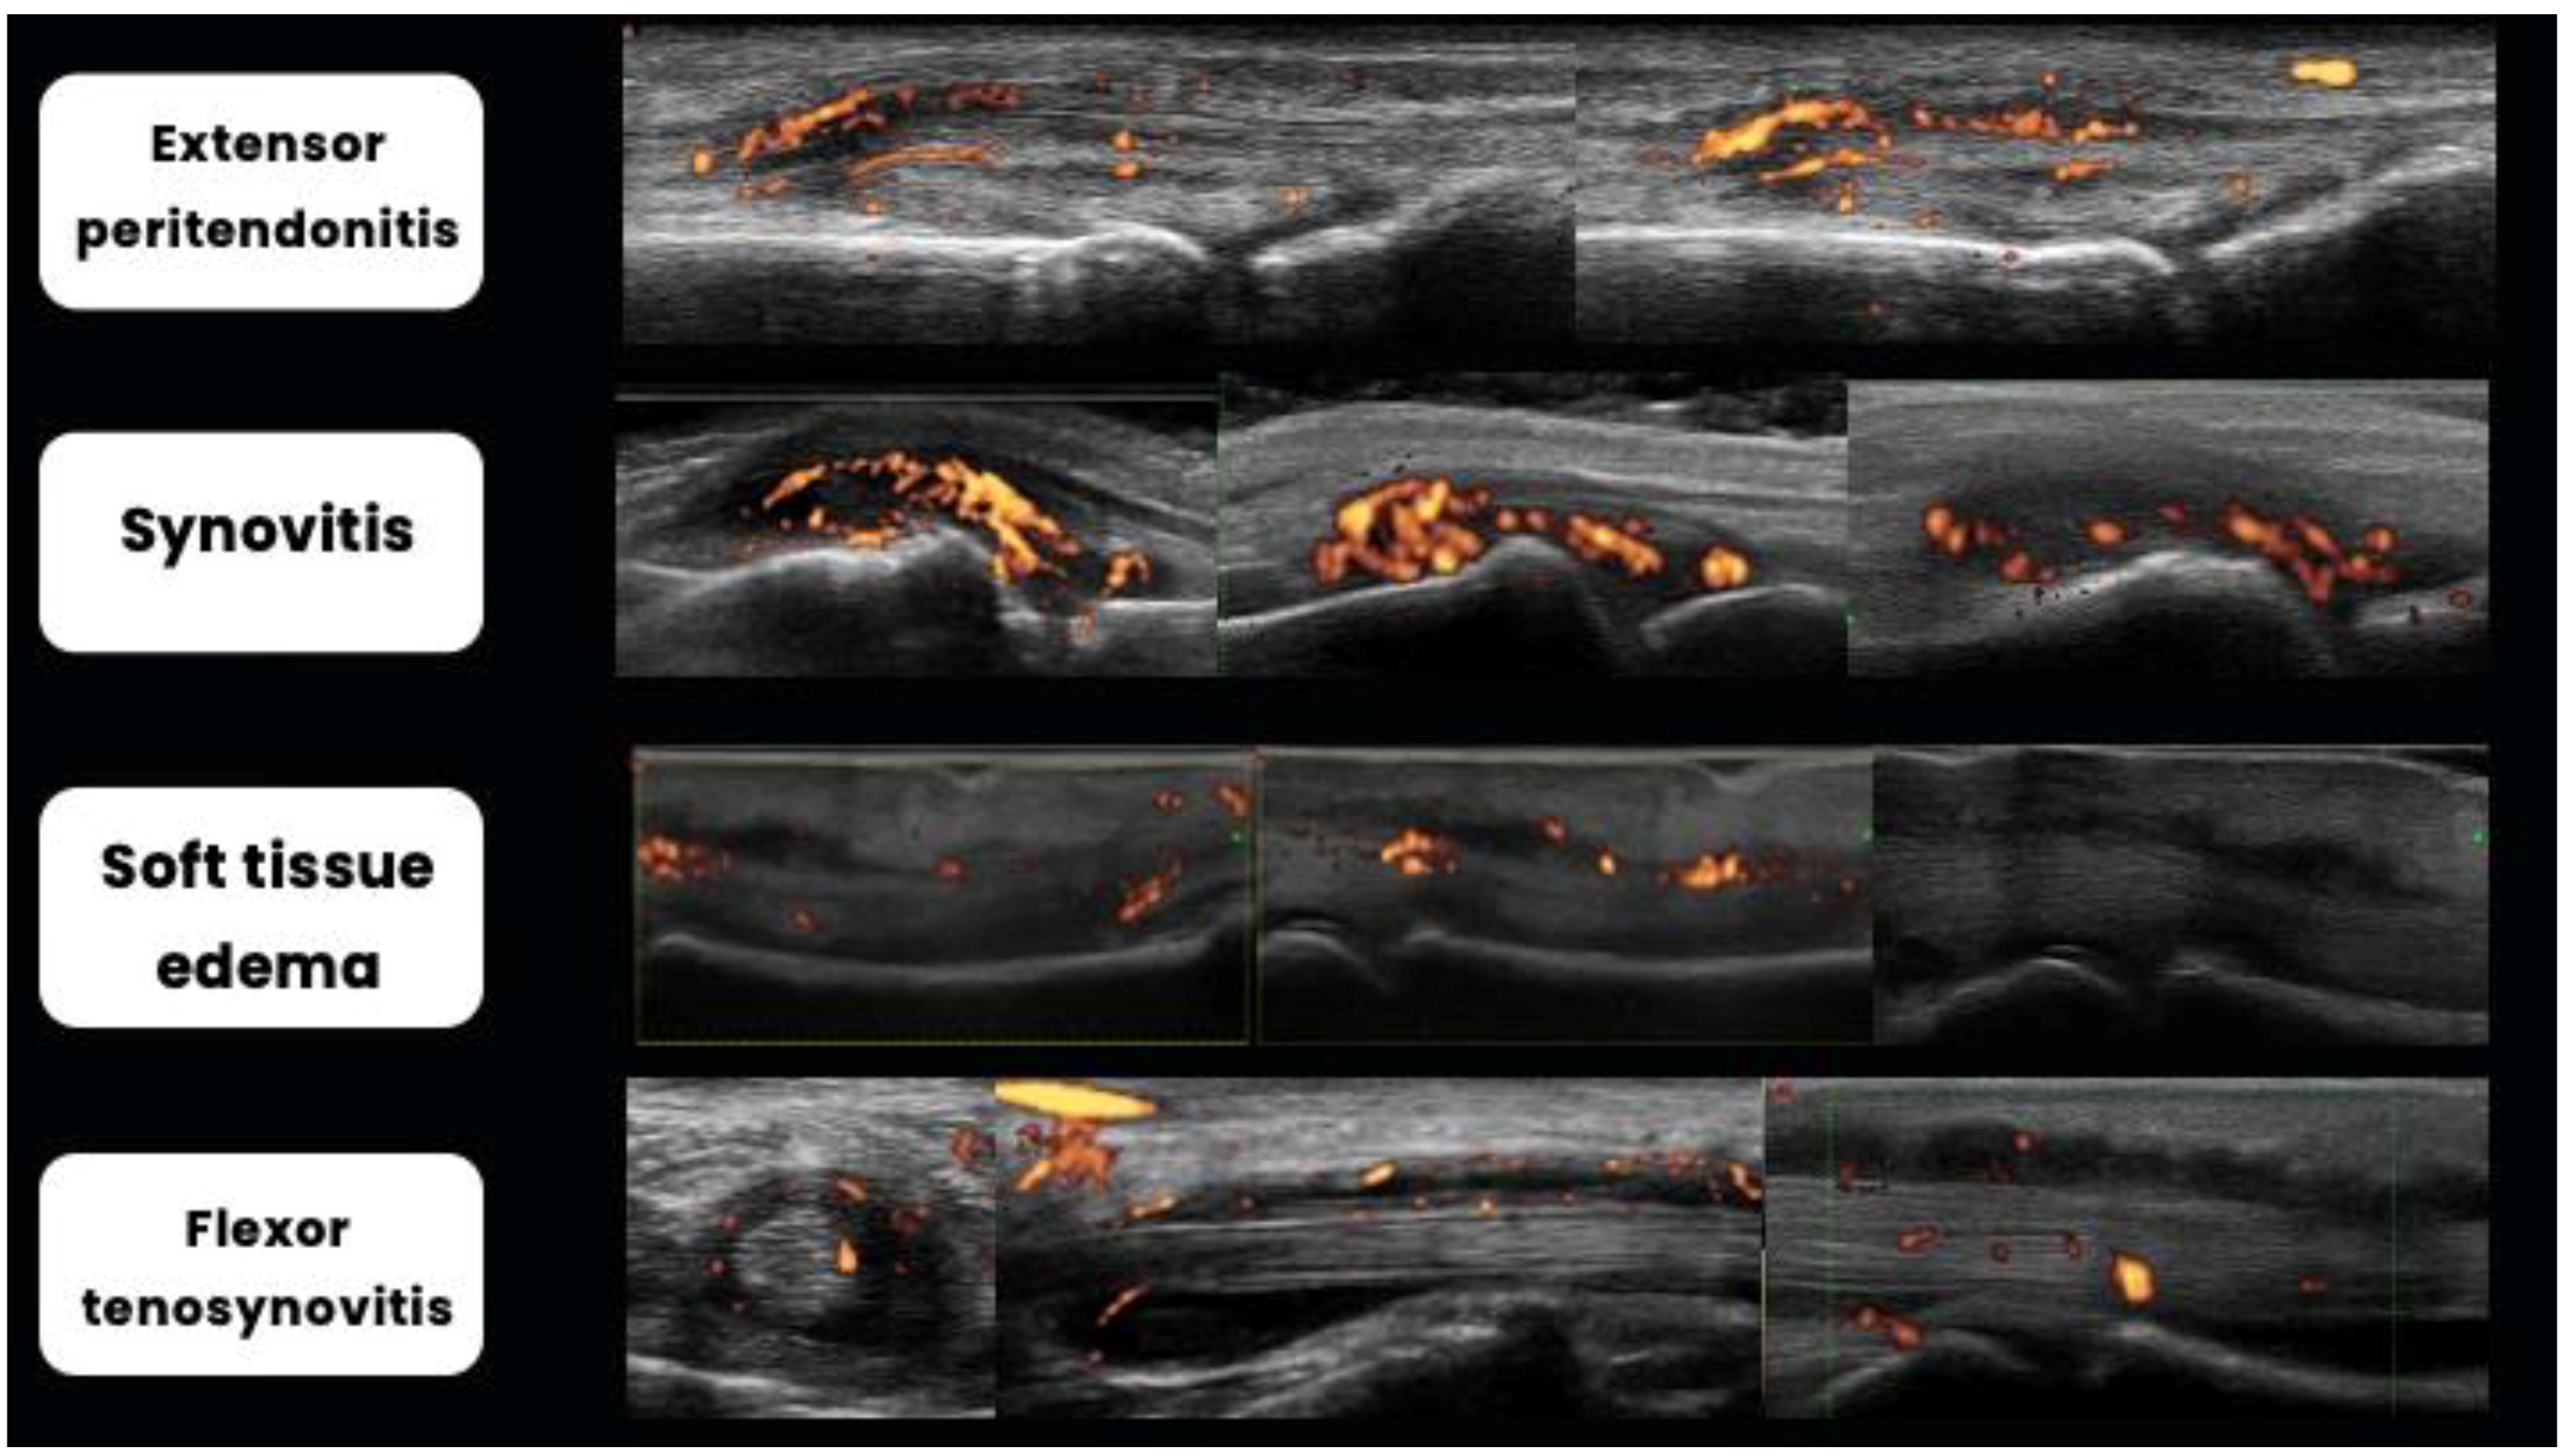

2.4. Tenosynovitis, Peritendinitis, and Functional Enthesitis

2.5. Dactylitis

- Zabotti, A.; Tinazzi, I.; Aydin, S.Z.; McGonagle, D. From Psoriasis to Psoriatic Arthritis: Insights from Imaging on the Transition to Psoriatic Arthritis and Implications for Arthritis Prevention. Curr. Rheumatol. Rep. 2020, 22, 24. [Google Scholar] [CrossRef] [PubMed]

- Tinazzi, I.; McGonagle, D.; Zabotti, A.; Chessa, D.; Marchetta, A.; Macchioni, P. Comprehensive evaluation of finger flexor tendon entheseal soft tissue and bone changes by ultrasound can differentiate psoriatic arthritis and rheu-matoid arthritis. Clin. Exp. Rheumatol. 2018, 36, 785–790. [Google Scholar]

- Tinazzi, I.; McGonagle, D.; Aydin, S.Z.; Chessa, D.; Marchetta, A.; Macchioni, P. “Deep Koebner” phenomenon of the flexor tendon-associated accessory pulleys as a novel factor in tenosynovitis and dactylitis in psoriatic arthritis. Ann. Rheum. Dis. 2018, 77, 922–925. [Google Scholar] [CrossRef] [PubMed]

- Tinazzi, I.; McGonagle, D.; Macchioni, P.; Aydin, S.Z. Power Doppler enhancement of accessory pulleys confirming disease localization in psoriatic dactylitis. Rheumatology 2020, 59, 2030–2034. [Google Scholar] [CrossRef]